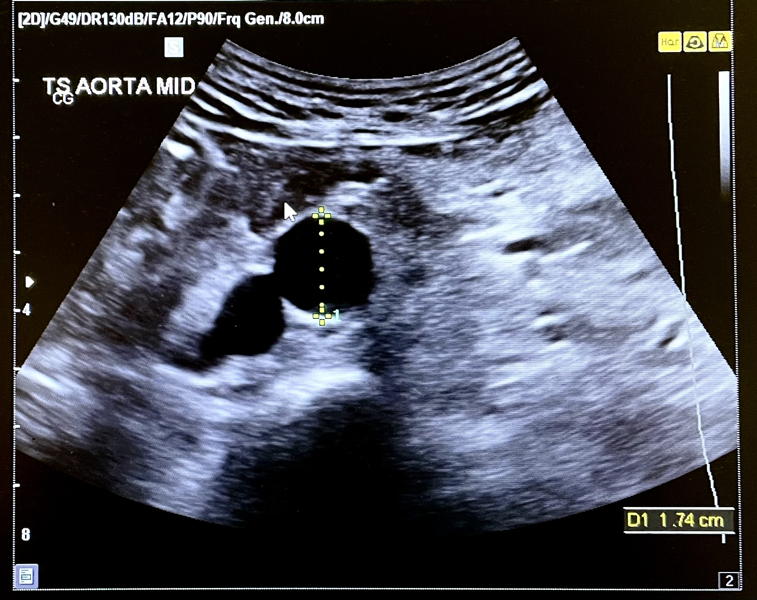

March brought still more medical attention. I was invited to attend an abdominal aorta aneurysm screening which sounded very dramatic but turned out to be a one-off ultrasound test for potential circulation problems, given to all 65-year olds. And I passed! Then I was off for a checkup at my new dentist, chosen because my previous surgery had descended into hopeless customer unfriendliness. A bit more expensive but efficient & professional, a definite improvement.